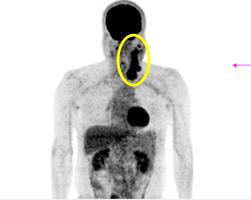

Hình ảnh PET/CT trước và sau điều trị

Hình 4: Trước điều trị: Hình ảnh khối hạch vùng cổ trái kích thước 10x12 cm, tăng hấp thu FDG mạnh (vòng tròn vàng).

Hình 5: Sau điều trị 4 tháng (6 chu kỳ hóa chất) : hình ảnh chụp PET/CT sau điều trị cho thấy khối hạch cổ trái tan biến hoàn toàn, không thấy tăng hấp thu FDG tại cơ quan bộ phận khác của cơ thể.

Hình 6: Sau điều trị 6 năm: hình ảnh chụp PET/CT sau điều trị cho thấy khối hạch cổ trái tan biến hoàn toàn, không thấy tăng hấp thu FDG tại cơ quan bộ phận khác của cơ thể.